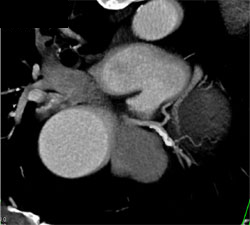

LAD Plaque